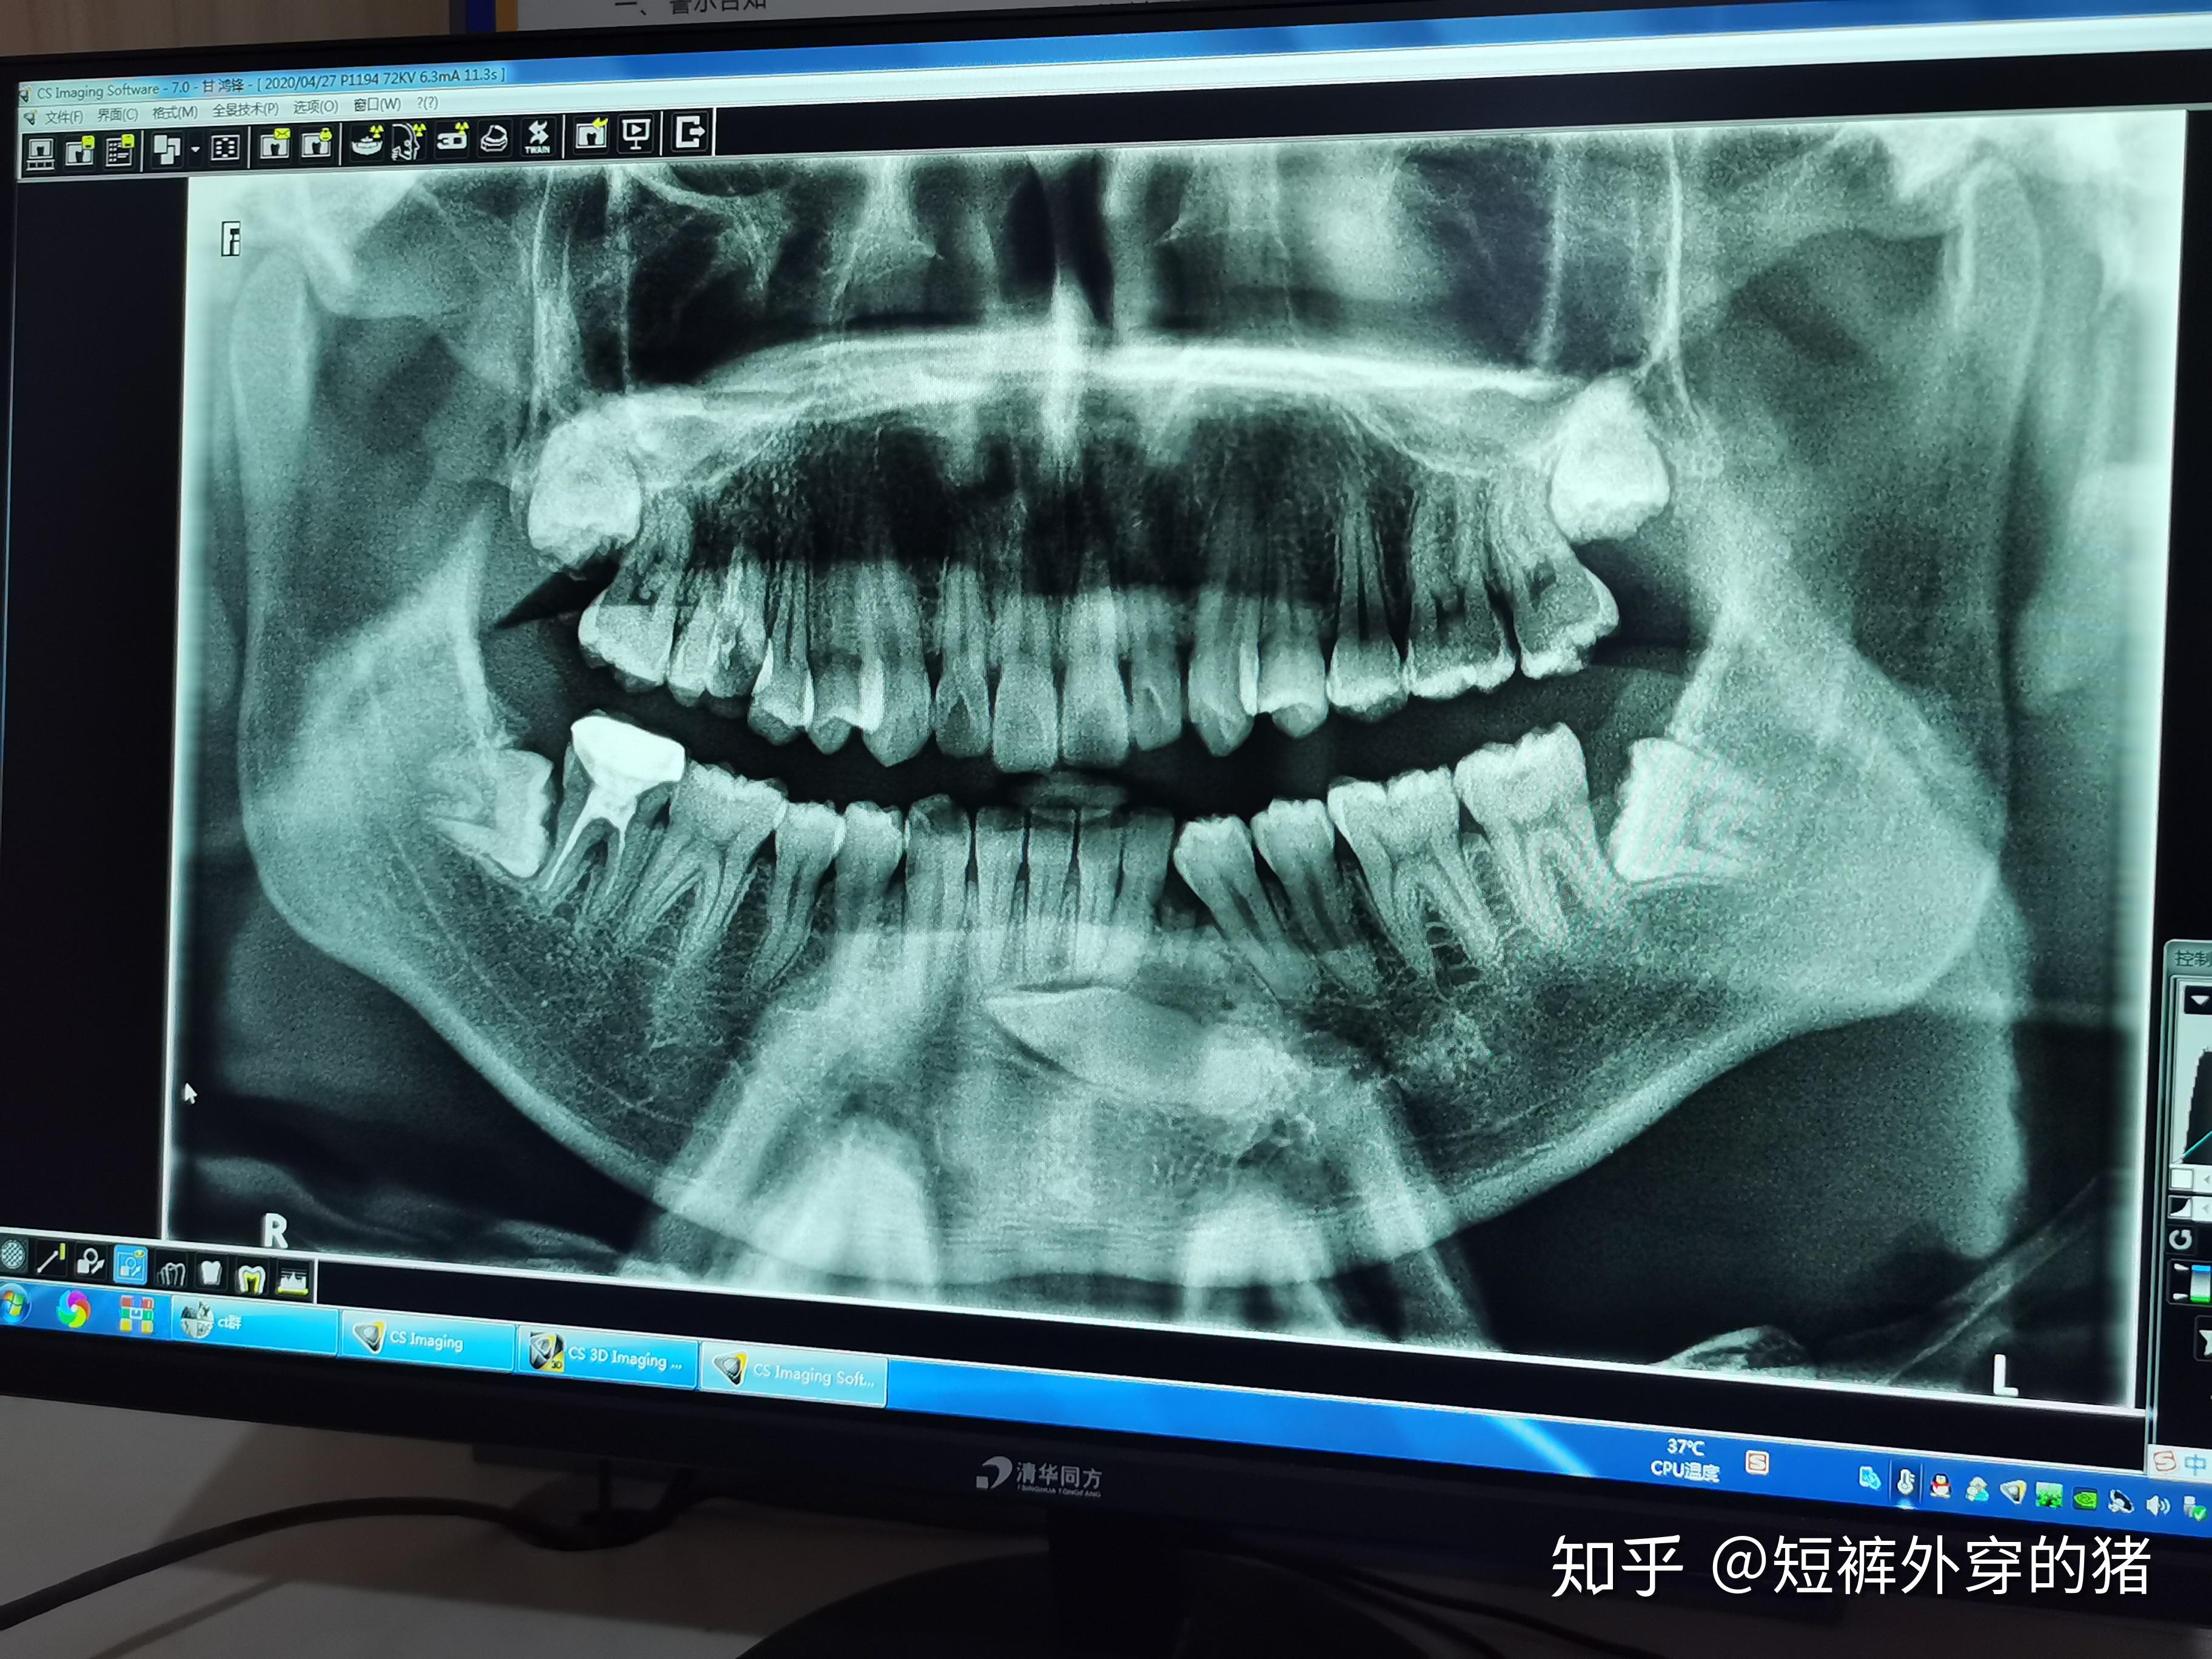

靠近下颌骨的位置有颗埋伏牙请问应该怎么治疗

下颌两侧智齿完全性骨埋伏阻生一例